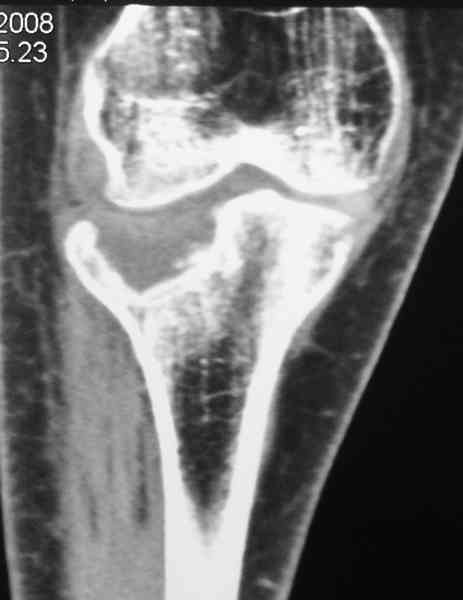

По тактике лечения, более импонирует второй вариант, но наружная плато расколота и туда при нагрузке внедряется н/мышелка бедра, поэтому после дистракции как репонирвать: или стяжными винтами, или изогнутами спицами или субхондральная костная пластика?

Уважаемый Абдурашид. Если нет противопоказаний , то из оперативных способов, я бы рекомендовал следующие: Полное замещение наружного мыщелка аллотрансплантатом либо открытая репозиция с элевацией и замещение дефекта ауто или аллокостью. В Ваших условиях , я бы рекомендовал второй способ. Во-время элевации необходимо разъединить фрагменты со стороны сустава ( надсечь скальпелем по линиям перелома, а затем тонким остеотомом их разъединить. При помощи долота произвести неполную остеотомию ( захватите не менее 1,5 - 2 см губчатой кости и поднять фрагменты, визуально отрепонировать и фиксировать 2-3 спицами. Дефект заместить костным ауто или аллатрансплантатом. Окончательная стабилизация пластиной ( лучше с угловой стабильностью, либо АВФ - позволит спокойно устранить угловую деформацию.